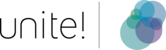

Figure 2: Research is being carried out in an interdisciplinary programme that brings together researchers specialising in neuroscience, structural biology, electrophysiology and biomedical engineering.

We hypothesise that stimulation of neuronal cells using light-activated photocaps promotes neuronal network formation and consequently enhances regeneration and neuroprotection after TBI. To test this hypothesis, we developed an interdisciplinary research programme that brings together specialists from the fields of neuroscience, structural biology, electrophysiology and biomedical engineering (see Figure 2). Cultured cells (Figure 3 shows a hippocampal slice culture placed on a multi-electrode array) are an invaluable tool for developing optimal stimulation parameters before shifting attention to healthy and injured brain tissue. We will investigate the optimal time window after TBI in which stimulation yields the most extensive regenerative results.